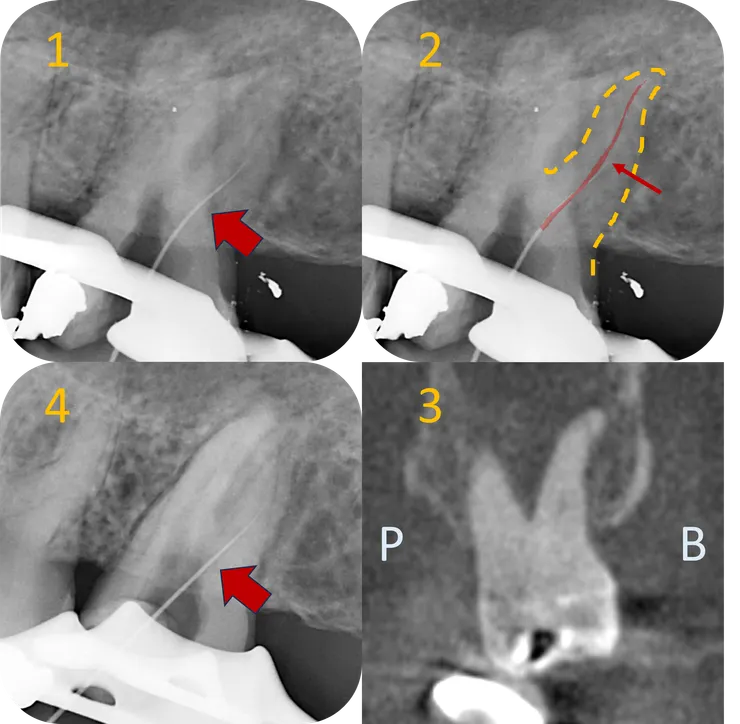

總結這兩顆的治療歷程:

1. Initial.

2. 第一次 RCF 後過了六年,36 distal apical lesion 顯著 healing.

3. 我接手後,歷經一年九個月,12 個 appointment 的治療,完成了這兩顆的 retreatment.

4. 一年後的追蹤,36 & 37 的 apical lesion 皆顯著癒合。

找到入口才只是剛開始,急著把 file 督進去找路也只會像前一位醫師一樣被卡在半路。

因此,在 file 進去前,必須先 coronal enlarge 以創造 file 的自由度。

在這裡,我使用 (想修掉哪裡就修掉那裡的) Komet endo Tracer bur 把從 distal 蓋過來的 covering dentin 修掉,再依序使用 Aurum blue CF --> PTG S1 --> S2 --> F1 --> F2 做到 ledge 所在的深度 (14.5mm),讓 file 在 ledge 以上完全自由......

然而此時 file (19mm #8 C pilot) 一進去還是被卡住找不到路......

一番掙扎後決定拍張 X 光片看看 ---

結果發現到達的深度跟前一位醫師一模模一樣樣...... (比較圖 1 & 4)

然而不同的是,經過 coronal enlarge 後,此時 file 的自由度變大了 (注意到紅色箭頭所指的 orifice 附近的彎度變直了),file tip 的手感就變清晰了!

再搭配圖 2 得知路徑應往 mesial 修正,搭配圖 3 得知 canal 中段以下往 buccal 彎,於是我在 file tip 1mm 處彎了一個小小彎,往 M/B 方向找 --->

就找到了原本的 pathway 完成了這個 case.

比較左右兩圖可以發現 DB orifice 選擇性地往 DB 擴大了許多 (而非以 orifice 為中心均勻擴大),使得 file 得到足夠的自由度得以找到 ledge 以下那個位於 B/M side 的 original pathway.

最後來檢討一下治療結果:

比較 DB canal 以及 MB & MB2 canal, 可以發現 DB canal 的修形相對保守許多。

其實以這顆的初始條件看來,MB & MB2 的修形是可以更加保守的......

若是在一開始治療前,就可以好好地把這顆的 root form & canal path 如中圖那般好好地描摹出來 (有 CBCT 則更好!),就可以以終為始地,依據每個 canal 的型態, 分別打造出最恰到好處的入口修型!如此一來,就可以在大幅縮短治療時間的同時,也保留更多齒質!